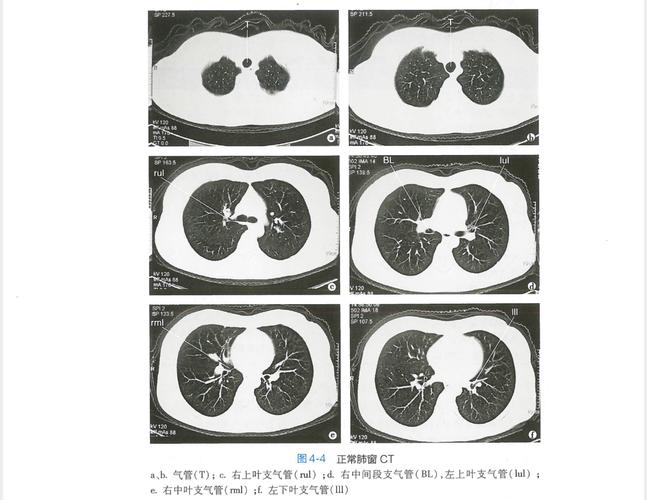

正常的肺部ct图片 讲解

正常的肺部ct图片 讲解,肺部ct图片讲解解读

jp-0184c胸部ct解剖(肺窗)